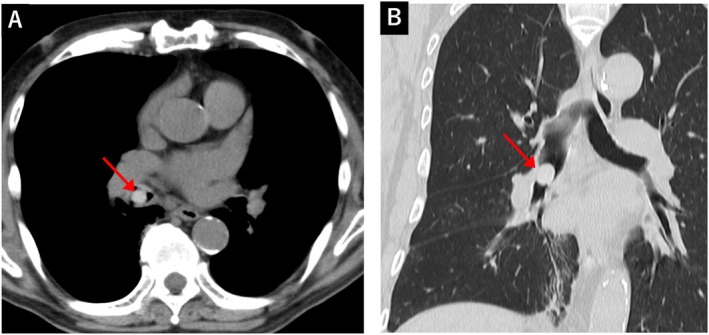

An 85-year-old man presented with a persistent cough accompanied by sputum production. He was initially treated with antibiotics and expectorants but showed no improvement. Chest computed tomography revealed a dense nodule in the right bronchus intermedius. On detailed history-taking, he recalled eating mukago-a small edible bulbil of Dioscorea japonica that is occasionally consumed in Japan-shortly before symptom onset. Flexible bronchoscopy identified an oval, hard foreign body lodged in the bronchus, which was successfully removed using biopsy forceps. The extracted object was confirmed to be a mukago. His cough disappeared after removal. Our case highlights the importance of considering foreign body aspiration in elderly patients presenting with unexplained chronic cough, even in the absence of overt choking episodes. Thorough dietary history-taking, appropriate imaging, and bronchoscopy are essential for timely diagnosis and effective management of foreign body aspiration.